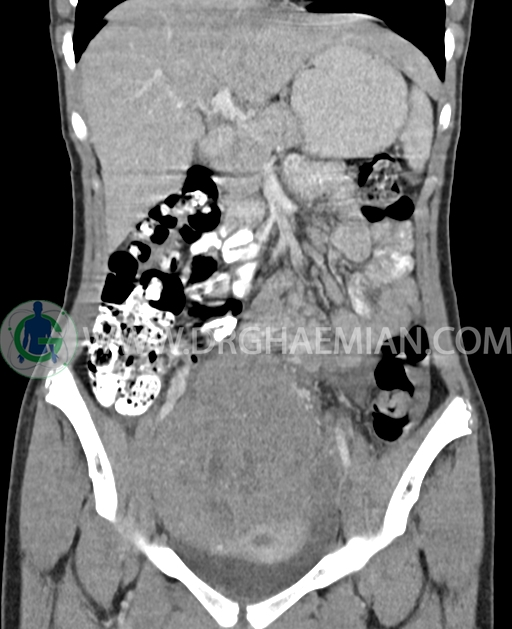

سی تی اسکن شکم و لگن از تشعشعات برای ایجاد تصاویر عرضی مقطعی از نایحه شکم و بین استخوان های لگن استفاده می کند. در این کیس تومور سلول زایا به ابعاد mm 125 x 112 x 80 دیده می شود.

در سی تی اسکن اسپیرال شکم و لگن با کنتراست خوراکی و وریدی (مولتی دیدکتور 16 با مقاطع ظریف و بازسازی های ساژیتال و کرونال) :

توده هیپردنس لوبوله بزرگ به ابعاد 125x112x80mm حاوی نواحی سیستیک داخلی و enhancement قابل توجه پریفرال همراه با آسیت متوسط در فضای شکم و لگن با احتمال بیشتر با منشا از تخمدان راست، درون لگن دیده می شود که در درجه اول مطرح کننده germ cell tumor می باشد .